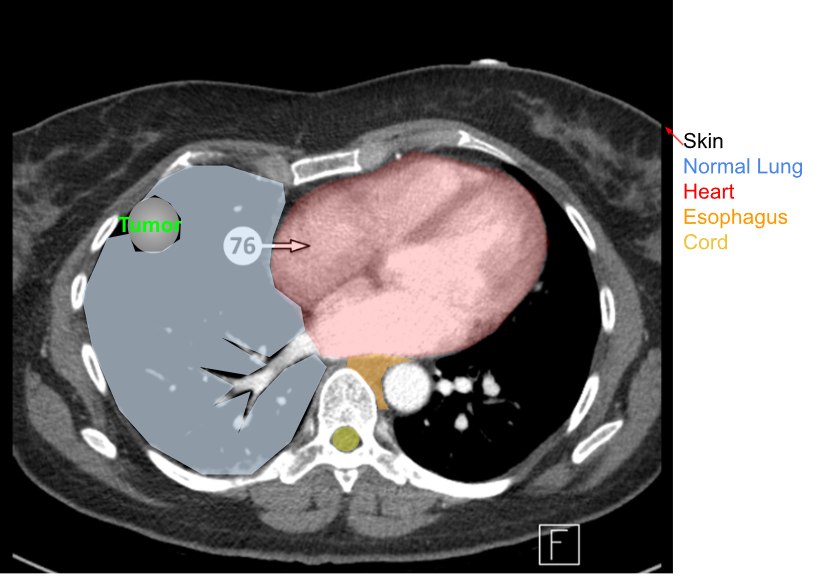

What normal anatomy is involved in a typical lung field? (i.e. normal tissue that also gets irradiated)

normal lung tissue

esophagus

heart

spinal cord

skin